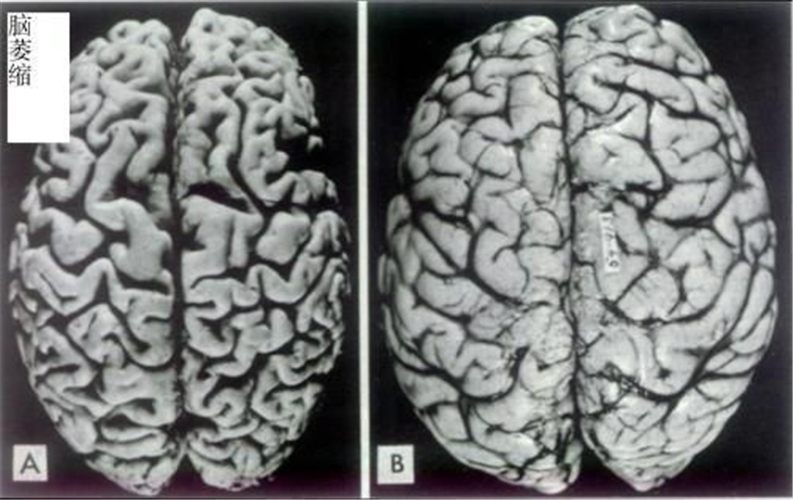

先天性腦萎縮與正常大腦對比